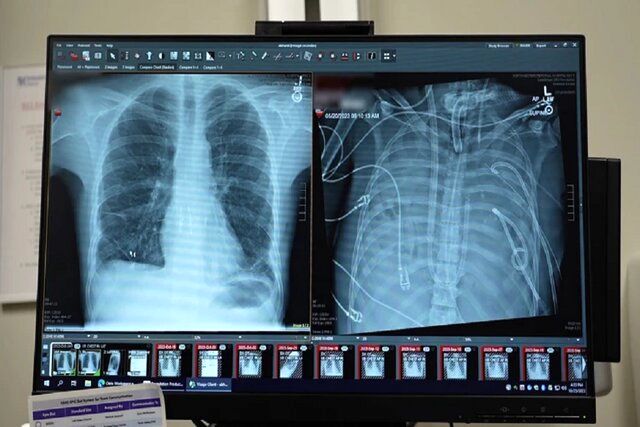

قبل از قرار گرفتن روی سیستم ریه مصنوعی، این مرد دچار سندرم حاد دیسترس تنفسی شده بود که یک وضعیت اغلب تهدیدکننده حیات است که در آن ریه‌ها نمی‌توانند اکسیژن کافی جذب کنند و این مشکل توسط ویروس آنفلوانزا ایجاد شده بود. سپس او روی ونتیلاتور قرار گرفت، اما دچار عفونت مقاوم به دارو شد. این عفونت باعث شد قسمت‌هایی از ریه‌های او پر از چرک شود و او وارد شوک سپتیک شود که در این مرحله قلب و کلیه‌هایش شروع به از کار افتادن کردند.

بهارات می‌گوید: او خیلی بیمار بود، دچار ایست قلبی شد و در حال مرگ بود. از آنجا که این مرد خیلی بیمار بود که پیوند ریه دریافت کند، گروه پزشکان تصمیم گرفتند ریه‌های او را که منبع عفونت بود، بردارند.

به طور شگفت‌انگیز، مرد شروع به بهبود سریع کرد. در عرض ۴۸ ساعت، او همه داروها برای حمایت از فشار خون را کنار گذاشت، عملکرد کلیه او کاملا بازیابی شد و قلب او به طور طبیعی کار می‌کرد. در این مرحله، مرد پیوند دو ریه را دریافت کرد و سال‌ها بعد هیچ نشانه‌ای از رد عضو یا اختلال عملکرد ریه نشان نداد. اکنون تقریبا سه سال از انجام این کار گذشته است و حال بیمار واقعا خوب است.